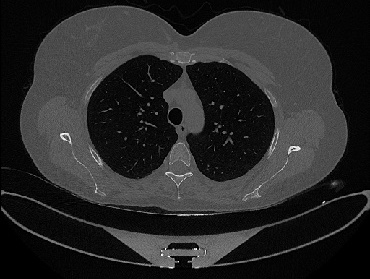

Figure 1 shows four CT scan slices, two from a non-COVID-19 CT scan, on the left and two from a COVID-19 scan, on the right. Bilateral ground glass regions are seen especially in lower lung lobes in the COVID-19 slices.